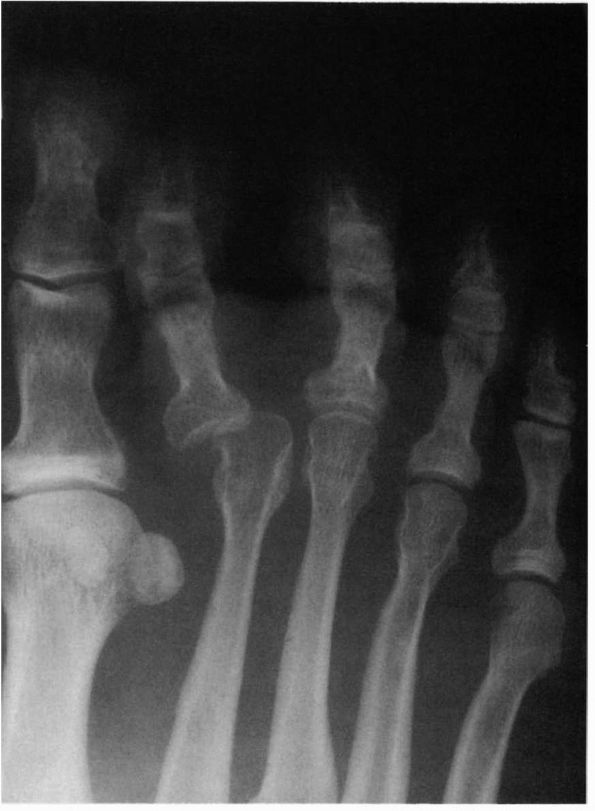

origin that occurs in the metatarsal head. This infarction results in

collapse of the metatarsophalangeal joint (Figure 21-15).

This process is often associated with generalized discomfort around the

joint, and the joint may develop a significant synovial reaction or

enlargement due to collapse of the bony structures. This condition can

often be managed conservatively with adequate shoes and padding,

although nonsteroidal anti-inflammatory medications are useful during

the acute phases. If the problem significantly limits the patient,

arthroplasty may be indicated to remove some of the proliferative bone

about the joint.